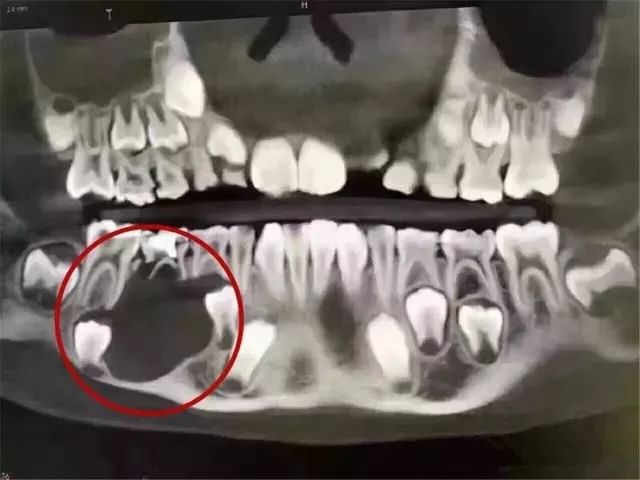

一位9岁的孩子,因父母没有重视乳牙护理和龋齿治疗,那颗乳牙下面的颌骨大面积吸收!当然,囊肿造成的但乳牙根尖周炎,也可能是这种吸收的可能原因之一(由于没有详细资料和医生的诊断)。

图像上黑色的阴影部分是下颌骨大面积破坏后的成像,太可怕了